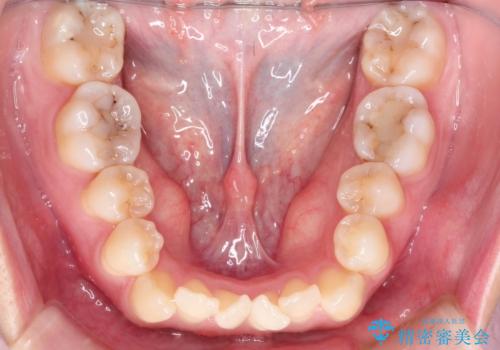

- 前歯がガタガタなのと、前歯でものが噛めないことを主訴に来院されました。

前歯の叢生があり、上下の前歯が接触していない開咬という状態でした。

左側の上下の前から4番目の歯を抜歯して、矯正することとしました。